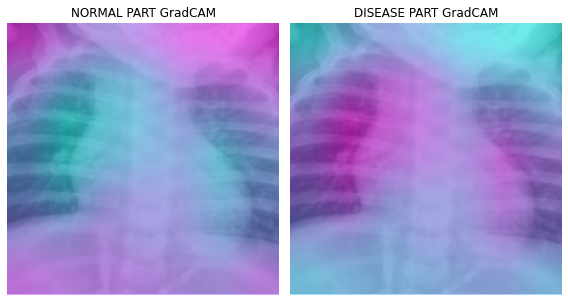

cam_xgradcam = xgradcam(input_tensor=x,targets=None)cam_eigencam = eigencam(input_tensor=x,targets=None)cam_fullgrad = fullgrad(input_tensor=x,targets=None)cam_eigengradcam = eigengradcam(input_tensor=x,targets=None)cam_layercam = layercam(input_tensor=x,targets=None)fig, (ax1,ax2) = plt.subplots(1,2)

dls.train.decode((x,))[0].squeeze().show(ax=ax1)

ax1.imshow(-cam_gradcam.squeeze(),alpha=0.5,extent=(0,224,224,0),interpolation='bilinear',cmap='cool')

ax1.set_title("NORMAL PART GradCAM")

#

dls.train.decode((x,))[0].squeeze().show(ax=ax2)

ax2.imshow(cam_gradcam.squeeze(),alpha=0.5,extent=(0,224,224,0),interpolation='bilinear',cmap='cool')

ax2.set_title("DISEASE PART GradCAM")

fig.set_figwidth(8)

fig.set_figheight(8)

fig.tight_layout()